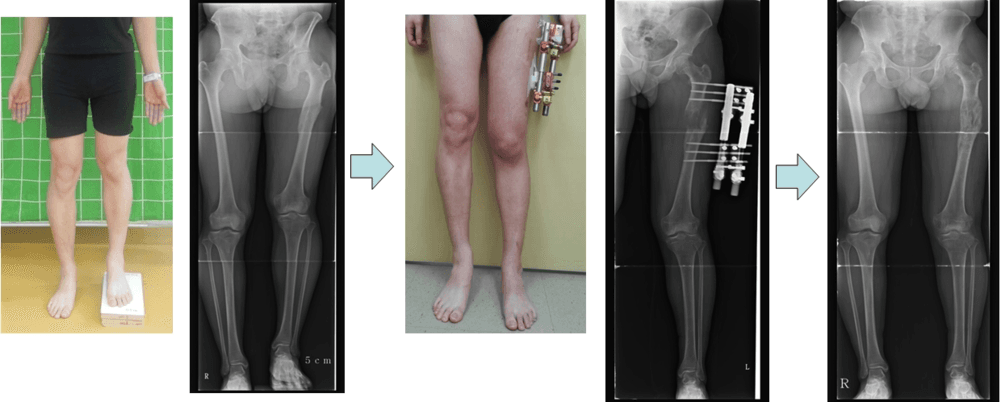

Femoral Lengthening in Patient with Leg Length Discrepancy